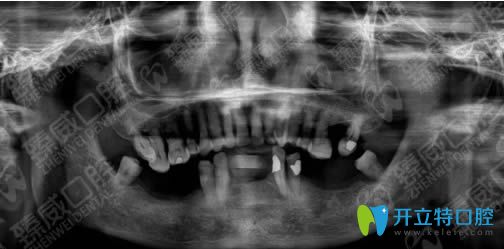

<下圖是我種植牙前的口腔CT片>:

我的下顎牙床已萎縮,上頜牙還都能要硬東西,但下頜牙松動(dòng)的難以咀嚼食物,只能吃一些稀爛的飯菜......魏東醫(yī)生考慮到我身體耐力差等身體因素,為我定制下頜all-on-4即拔即種修復(fù)方案,說(shuō)只需要4個(gè)種植體即可恢復(fù)半口牙。